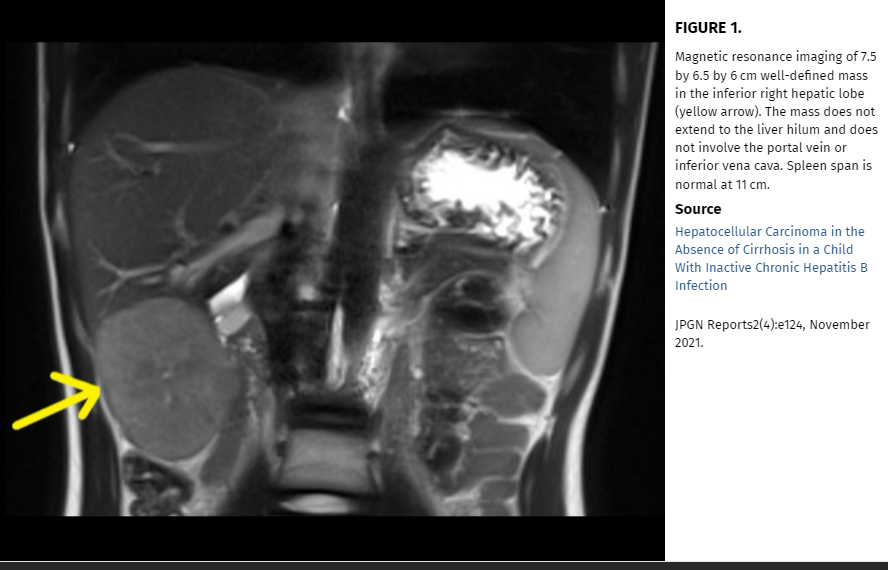

C Rajan et al. JPGN Reports: November 2021 – Volume 2 – Issue 4 – p e124. Open Access: Hepatocellular Carcinoma in the Absence of Cirrhosis in a Child With Inactive Chronic Hepatitis B Infection

In this case study, the authors “describe an unusual case of a child with chronic hepatitis B infection who developed HCC in the absence of active hepatitis or cirrhosis.” Based on their case report, they advocate for “regular HCC surveillance for all children with chronic hepatitis B, regardless of presence or absence of hepatitis or cirrhosis.”